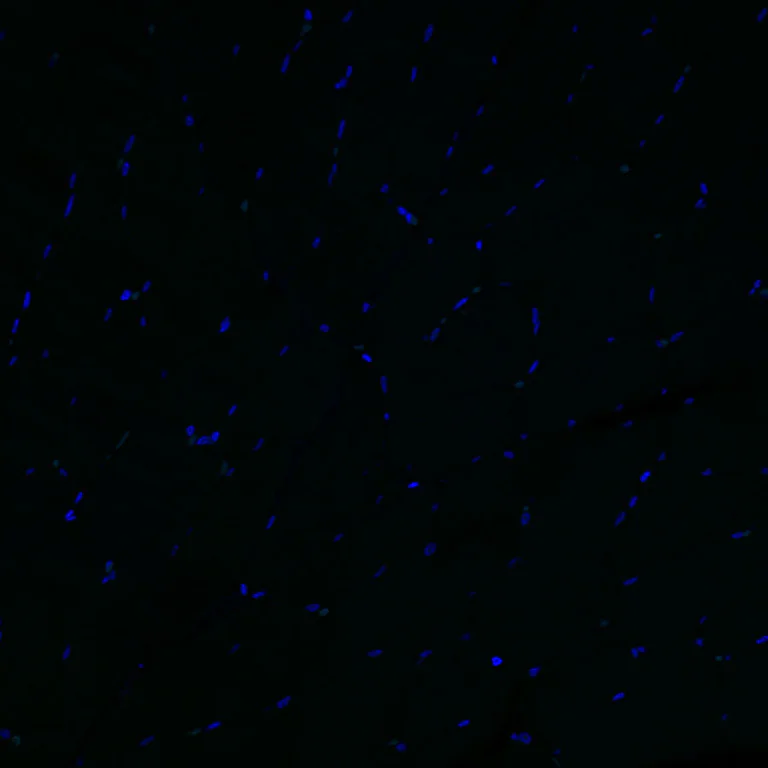

Immunohistochemical analysis of paraffin-embedded Human skeletal muscle tissue labeling Aquaporin 5 with ab308598 at 1/100 (5.0 ug/ml). Negative control : no staining on human skeletal muscle. The section was incubated with ab308598 for 60 mins at room temperature (shown in green). Nuclear DNA was labeled with DAPI (shown in blue). The section was then mounted using Fluoromount®.The immunostaining was performed on a Leica Biosystems BOND RX instrument. Image was taken with a confocal microscope (Leica-Microsystems, TCS SP8). Heat mediated antigen retrieval was performed with Tris-EDTA buffer (pH 9.0, Epitope Retrieval Solution2) for 40 mins.